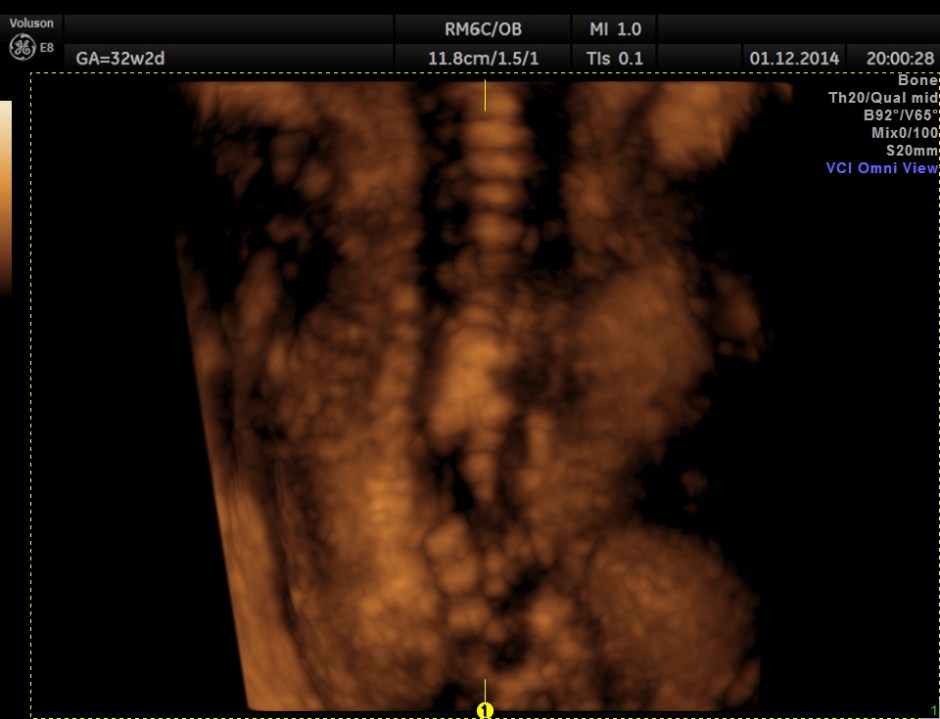

3D view of the same.

Careful examination revealed a neural tube defect with meningo myelocele at the lumbo sacral level.

Spinal deformity was also noted.